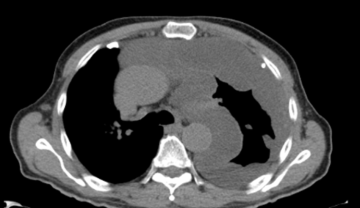

CT scan showing pleural effusion (fluid buildup) around the left lung, which can be a sign of mesothelioma.

CT Scan

A CT scan is commonly used to help diagnose mesothelioma by providing detailed images of the chest or abdomen.